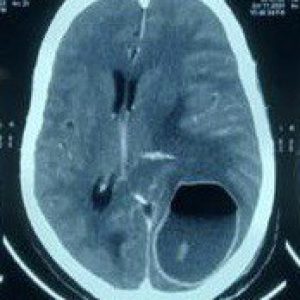

Photo Gallery